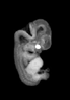

Animations

MRI Slice Selector